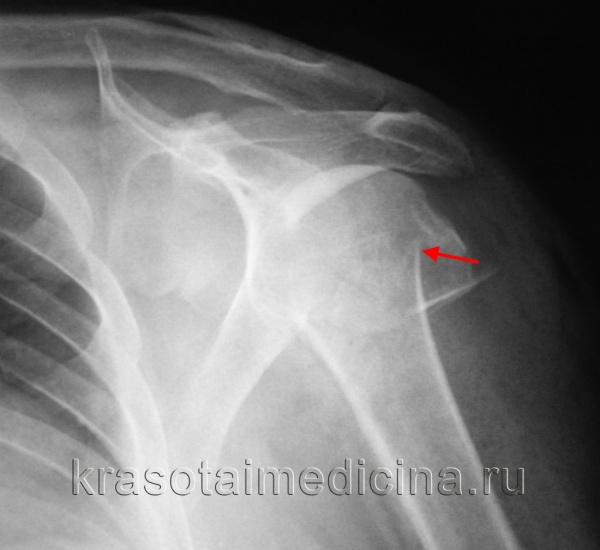

В норме угол между головкой и диафизом плечевой кости составляет 135°. Важно, чтобы врач, занимающийся лечением перелома проксимального отдела плечевой кости, измерил этот угол. Угол 90° и меньше или равный 180° и больше считают значительно отличающимся от нормы; в зависимости от возраста и активности больного может потребоваться репозиция. Переломы хирургической шейки можно разделить на три класса.

Класс А: вколоченные переломы хирургической шейки плечевой кости с угловым смещением. Угловая деформация менее 45° не подлежит репозиции. Последняя показана при превышении 45 градусов в зависимости от возраста и активности больного.

Класс Б: переломы хирургической шейки плечевой кости со смещением по ширине. Переломы с расхождением фрагментов более чем на 1 см считают переломами со смещением. В свою очередь их подразделяют на абдукционные и аддукционные в зависимости от положения диафиза плечевой кости.

Класс В: оскольчатые переломы хирургической шейки плечевой кости. Оскольчатые переломы не всегда выглядят так, как изображено на рисунке.